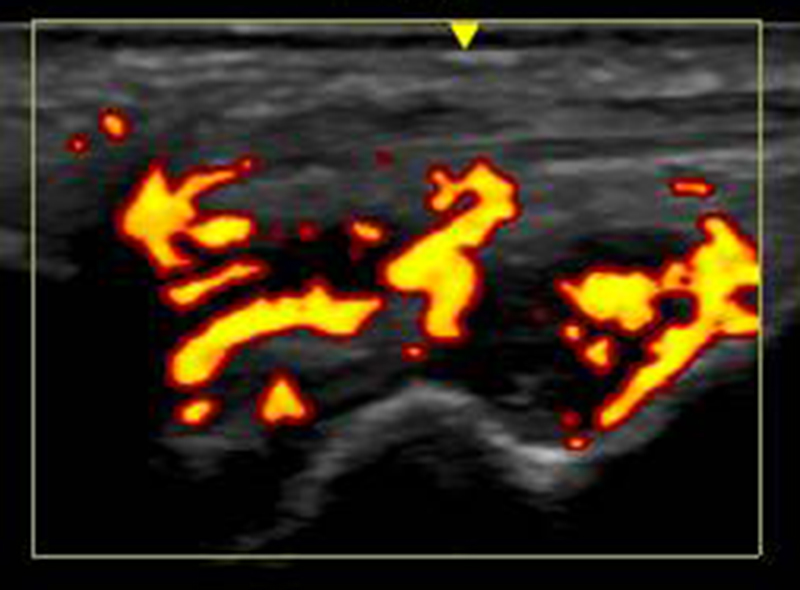

レントゲンや超音波診断も有効です。